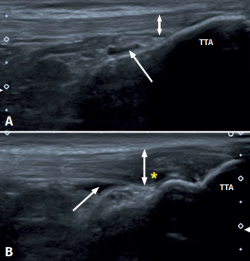

Figure 1. Ultrasound images (linear probe) of the patellar tendon, distal portion. Longitudinal view of the tendon fibres at insertion in the anterior tibial tuberosity (ATT). A: distal insertion of the normal patellar tendon. The arrow shows mild bursitis, and the double arrow indicates the normal size of the tendon; B: distal patellar tendinopathy showing the deep infrapatellar bursa (arrow) containing fluid (hypoechoic image), with increased tendon thickness (double arrow) and a fibrillar pattern showing decreased echogenicity (hypoechoic) secondary to disruption of the collagen bands (asterisk).

Distal PT in the adult (Figure 1) is also found as a complication of Osgood-Schlatter disease. This form of osteochondritis of the anterior tibial tuberosity manifests at prepubertal ages (males: 12-15 years; females: 8-13 years), it is produced by traction of the tendon upon its distal insertion in the distal tuberosity of the tibia, and is characterised by pain in response to palpation of the anterior tibial tuberosity in the physical examination(13). Its appearance has also been described at 12-18 months, before the completion of skeletal maturation(14).